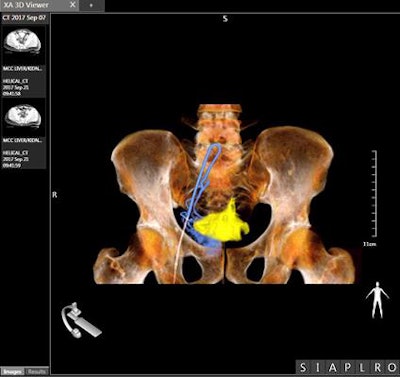

Alphenix is an interventional angiography platform that Canon Medical Systems is highlighting at the congress in Vienna. Enhancements include a conebeam CT mode called AlphaCT for low-contrast imaging and a real-time autopixel shift mode that cleans up imaging in less than 10 msec. The platform also includes the Hi-Def Detector, a flat-panel digital detector available on the Alphenix Biplane and Alphenix Core + systems.

An interventional suite that pairs an angiography system with a CT scanner -- called Alphenix 4D CT -- also is being demonstrated at the vendor's booth. The suite matches an Alphenix Sky + C-arm with an Aquilion One Genesis volumetric CT scanner, enabling clinicians to plan, verify, and treat patients in a single session.